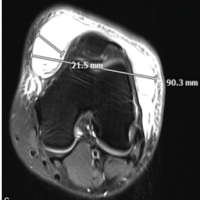

A synovectomy was performed using a motorized shaver. By interchanging the portals, the loose bodies were removed with a large grasper. Approximately 25 fragments, ranging from 2 mm to 18 mm in size, were removed (Fig. 3). Two of them were large, each measuring 18 mm; for such extensive fragments, straight artery forceps were used and were removed in a piecemeal fashion. After the removal of loose bodies, radiofrequency cauterization was done.